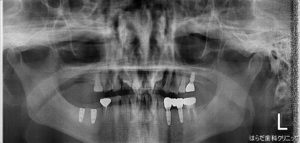

レントゲンの1枚目の写真は右下6,7番にインプラントを埋入する前のパノラマ写真です!

写真は左右反転してみて下さい。右下のところに歯がないのがわかります。

2枚目の写真はインプラントを埋入した後のパノラマ写真です!

こちを見て頂くと、右下6,7番にしっかりとインプラントが埋入されているのが分かります。